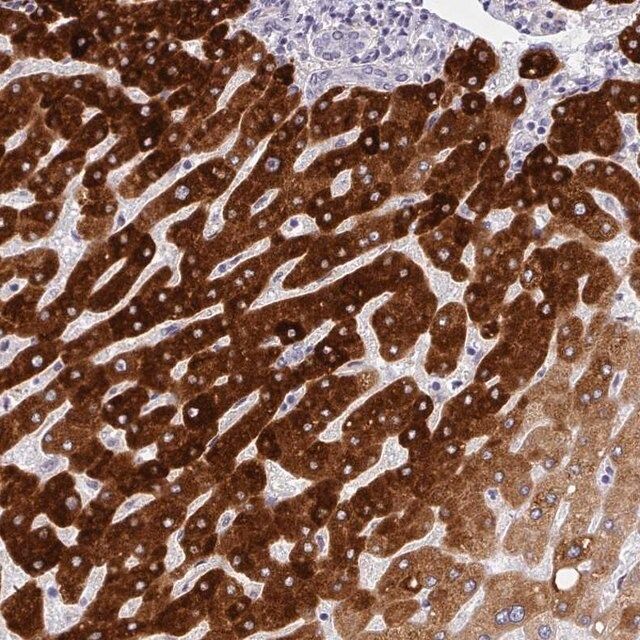

人类蛋白质图谱项目可细分为三个方面的工作:人类组织图谱、癌症图谱和人类细胞图谱。支持 Tissue and Cancer Atlas 项目而产生的抗体,已经通过免疫组化针对数百个正常和疾病组织进行了测试,通过 Human Cell Atlas 项目最近的努力,很多已经通过免疫荧光法进行了表征,不仅在组织级别,现在也在亚细胞级别绘制了人类蛋白质组图谱。通过点击图像库链接,可以在 Human Protein Atlas (HPA) 位点上查看这些图像和这个庞大数据集的集合。要查看这些协议 和其他有关 Prestige 抗体和 HPA 的有用信息,请访问sigma.com/prestige。

- 44例正常人类组织以及20例最常见癌症类型组织的IHC组织阵列。